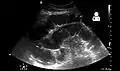

Radiological signs of bowel obstruction include bowel distension and the presence of multiple (more than six) gas-fluid levels on supine and erect abdominal radiographs. Ultrasounds may be as useful as CT scanning to make the diagnosis.[17]

- Small bowel obstruction on ultrasound[19]

Small bowel obstruction on ultrasound[19]